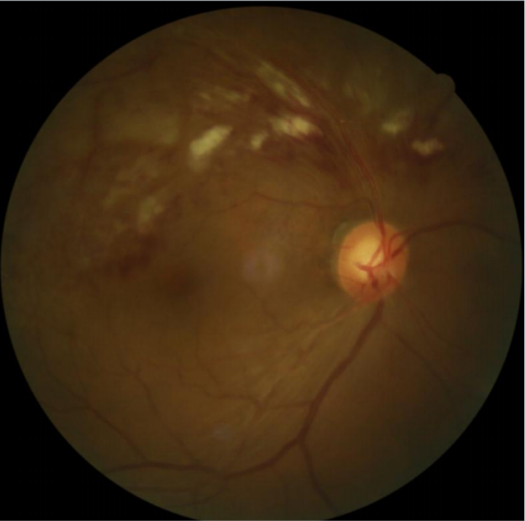

患者劉某,58歲,因右眼視力下降伴(bàn)變形1月入院。既往有高血壓病,血糖偏高病史,左眼視物(wù)不(bú)見10餘(yú)年,經過眼科主治醫(yī)師方(fāng)霏的(de)詳細檢查及(jí)眼底造(zào)影(yǐng)檢(jiǎn)查,發現是患(huàn)上了右眼視網膜分支靜脈阻塞,右眼黃斑水腫,左眼萎縮性黃斑病變(biàn)。劉大叔入院時右眼視力僅0.1 ,需要使用一種新型的生物製劑(jì)(抗 VEGF)治(zhì)療,方霏主治醫師向患者及(jí)家屬交代病情、手術(shù)必要性及相關風險 ,在排(pái)除(chú)了手術禁忌症後,患者及家屬表示同(tóng)意手術治療。次日,方霏主治醫師在患者(zhě)表麵麻醉下進行右(yòu)眼(yǎn)玻璃體藥物注射術,術後患者(zhě)無明顯特殊不適。4周後複查,右眼黃斑水腫明顯減輕,視力由0.1提高至0.6。玻璃體腔注藥術明顯改善了患者視力,患者劉大叔表示十分滿意。

術後4周眼(yǎn)底照相